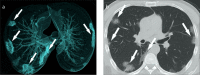

Results: A total of 250 patients were finally diagnosed with COVID-19. Clinical and laboratory findings included myalgia or fatigue (76%), fever (64.8%), dry cough (60.8%), elevated levels of C-reactive protein (86.4%), procalcitonin (62%), and D-dimer (58.2%), increased neutrophil-lymphocyte ratio (NLR) (54.8%), and lymphopenia (34%). Sensitivity, specificity, positive predictive value (PPV) and negative predictive value (NPV) of the initial CT scan were 90.4% (95% IC, 86%-93%), 64.2% (95% IC, 50%-76%), 91.8% (95% IC, 88%-94%), and 60% (95% IC, 49%-69%), respectively. The percentage of patients diagnosed on the initial rRT-PCR test was 51.6% (n=129). Most frequent CT characteristics of COVID-19 in the subgroup of rRT-PCR-positive patients were multiple lesion (97.4%, n=220), followed by bilateral involvement (88.5%, n=200), peripheral distribution (74.3%, n=168), ground-glass opacity (GGO) (69.2%, n=157), subpleural curvilinear opacity (41.6%, n=104), and mixed GGOs (27.6%, n=67).